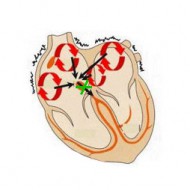

Szív vezetési rendszer képviseli idegrostok keresztül impulzusvezetés lépés egy szigorúan meghatározott irányban - a pitvarok a kamrákba. Ez biztosítja szinkron munka minden kamarák a szív. Ha akadályokba ütközik a szívizomban (hegek, például), további kötegek alakult méhen belül, összehúzó mechanizmusok törött és vannak előfeltételei a ritmuszavar.

a különböző aritmiák, ami MAC-szindróma